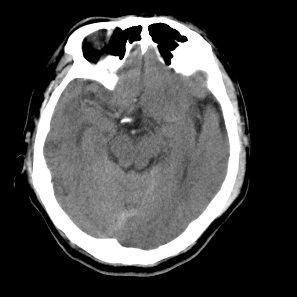

标题: CT18598:男47岁头晕头痛,烦操不安 [打印本页]

标题: CT18598:男47岁头晕头痛,烦操不安

右侧颞顶枕叶缺血性脑梗塞可能性大,建议增强进一步检查。

右侧颞顶叶脑沟变浅,片状低密度区内见略高密度影,考虑出血性脑梗塞,及时复查.

右侧颞顶枕叶脑梗塞可能性大,建议增强进一步检查

右侧颞顶枕叶缺血性脑梗塞可能性大,建议增强进一步检查排除转移瘤。

右大脑多处低密度水肿灶,无明显占位效应,病灶分布于不同大脑动脉供血区域!多发性脑转移瘤.(ct+或mri可进一步验证).

考虑右侧颞顶枕叶交界处脑梗塞可能性大。

考虑分水岭梗塞,建议增强排除其他

右侧颞顶枕叶缺血性脑梗塞